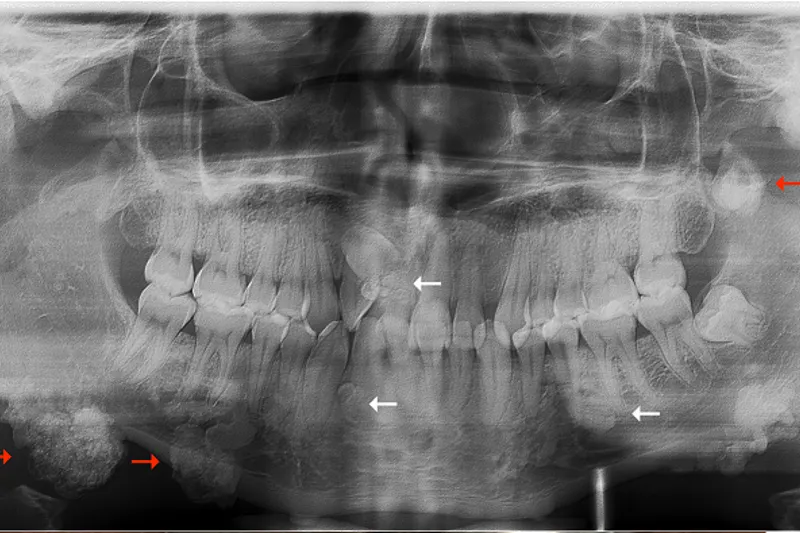

BAGGRUND – Familiær adenomatøs polypose er en sjældent forekommende arvelig tarmsygdom, som er karakteriseret ved udvikling af fra 100 til flere tusinde kolorektale polypper og ekstrakoloniske manifestationer, herunder osteomer i kæberne og tandanomalier.

PATIENTTILFÆLDE – En 29-årig mand blev henvist fra sin privatpraktiserende læge til Kæbekirurgisk Afdeling, Aalborg Universitetshospital, med henblik på diagnostik og behandling af let symptomgivende og kosmetisk skæmmende langsomt voksende hårde hævelser bilateralt langs basis mandibulae.

Patienten var kendt med familiær adenomatøs polypose.

Histologisk undersøgelse af excisionsbiopsier viste forandringer forenelige med osteomer som led i familiær adenomatøs polypose.

Familiær adenomatøs polypose er en sjælden arvelig sygdom forårsaget af en gendefekt. Mutationen giver anledning til udvikling af kolorektale adenomer og forekomst af ekstrakoloniske manifestationer, heriblandt osteomer i kæberne og dentoalveolære forandringer. Osteomer i kæberne tillægges en prædiktiv værdi, fordi de ofte kan påvises hos børn og unge inden udviklingen af kolorektale adenomer. Ubehandlet udvikler alle patienter kolorektal cancer; derfor er kendskab til de kliniske og radiologiske afvigelser essentielt for at iværksætte tidlig diagnostik og behandling.